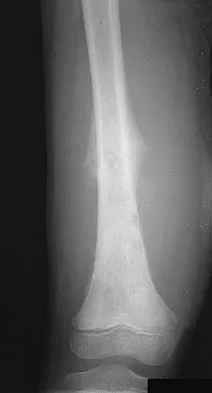

A 24-year-old woman was struck by a mini van in a parking lot and sustained a closed segmental tibia fracture that was treated with an intramedullary nail the following morning. Follow-up examinations reveal a slowly progressive clawing of all five toes, a progressive equinocavovarus contracture, and the patient is unable to perform a single heel rise on the affected limb. At 1 year after surgery, the patient now has a 10-degree equinus contracture that is not relieved with knee flexion. Treatment should now consist of

Explanation

This is an example of a missed deep posterior compartment syndrome that typically presents 6 months after the injury with progressive clawing due to necrosis, scarring, and contracture of the posterior tibial tendon, flexor digitorum longus, and flexor hallucis longus. Treatment consists of debridement of necrotic muscle and scar tissue with corresponding tendon excision. After debridement and posterior capsule release, if the equinus is relieved with knee flexion, a gastrocnemius slide may be performed. Otherwise, the lengthening should be at the level of the Achilles tendon. Bracing will not address the claw toes. Hansen ST Jr: Functional Reconstruction of the Foot and Ankle. Philadelphia, PA, Lippincott Williams & Wilkins, 2000, pp 212-213. Manoli A II, Smith DG, Hansen ST Jr: Scarred muscle excision for the treatment of established ischemic contracture of the lower extremity. Clin Orthop Relat Res 1993;292:309-314.